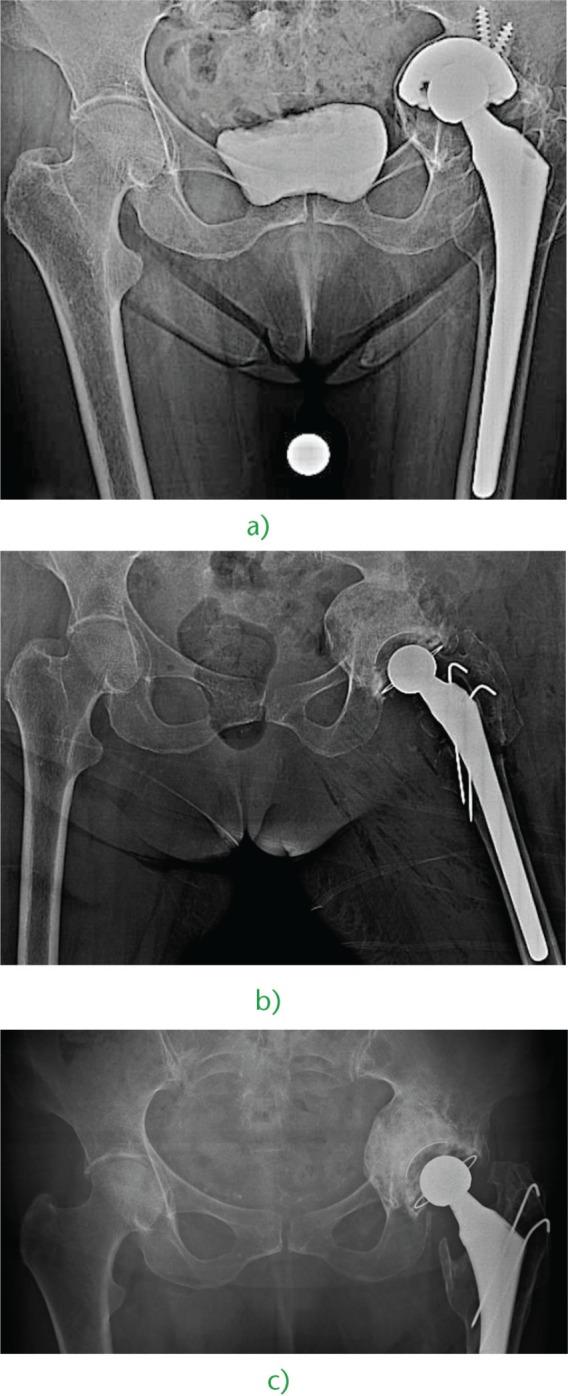

Acetabular bone loss is a relevant concern for surgeons dealing with a failed total hip arthroplasty.Since the femoral head is no longer available, allografts represent the first choice for most reconstructive solutions, either as a structural buttress or impacted bone chips.Even though fresh-frozen bone is firmly recommended for structural grafts, freeze-dried and/or irradiated bone may be used alternatively for impaction grafting. Indeed, there are some papers on freeze-dried or irradiated bone impaction grafting, but their number is limited, as is the number of cases.Xenografts do not represent a viable option based on the poor available evidence but bioactive bioceramics such as hydroxyapatite and biphasic calcium phosphates are suitable bone graft extenders or even substitutes for acetabular impaction grafting.Bone-marrow-derived mesenchymal stem cells and demineralised bone matrix seem to act as reliable bone graft enhancers, i.e. adjuvant therapies able to improve the biological performance of standard bone grafts or substitutes. Among these therapies, platelet-rich plasma and bone morphogenetic proteins need to be investigated further before any recommendations can be made. Cite this article: 2016;1:431-439. DOI:10.1302/2058-5241.160025.

髋臼骨缺损是髋关节置换失败的外科医生所面临的一个重要问题。由于股骨头已无法使用,同种异体骨移植成为大多数重建方案的首选,既可以作为结构性支撑物,也可以作为打压植骨的骨碎片。尽管强烈推荐使用新鲜冷冻骨进行结构性植骨,但冻干骨和/或辐照骨也可用于打压植骨。实际上,有一些关于冻干骨或辐照骨打压植骨的文献,但数量有限,病例数也不多。基于现有证据不足,异种骨移植不是一个可行的选择,但生物活性生物陶瓷,如羟基磷灰石和双相磷酸钙,是合适的骨移植增强剂,甚至可替代髋臼打压植骨。骨髓间充质干细胞和脱矿骨基质似乎是可靠的骨移植增强剂,即能够改善标准骨移植或替代物生物学性能的辅助治疗方法。在这些治疗方法中,富血小板血浆和骨形态发生蛋白在提出任何建议之前都需要进一步研究。引用本文:2016;1:431 - 439。DOI:10.1302/2058 - 5241.160025。